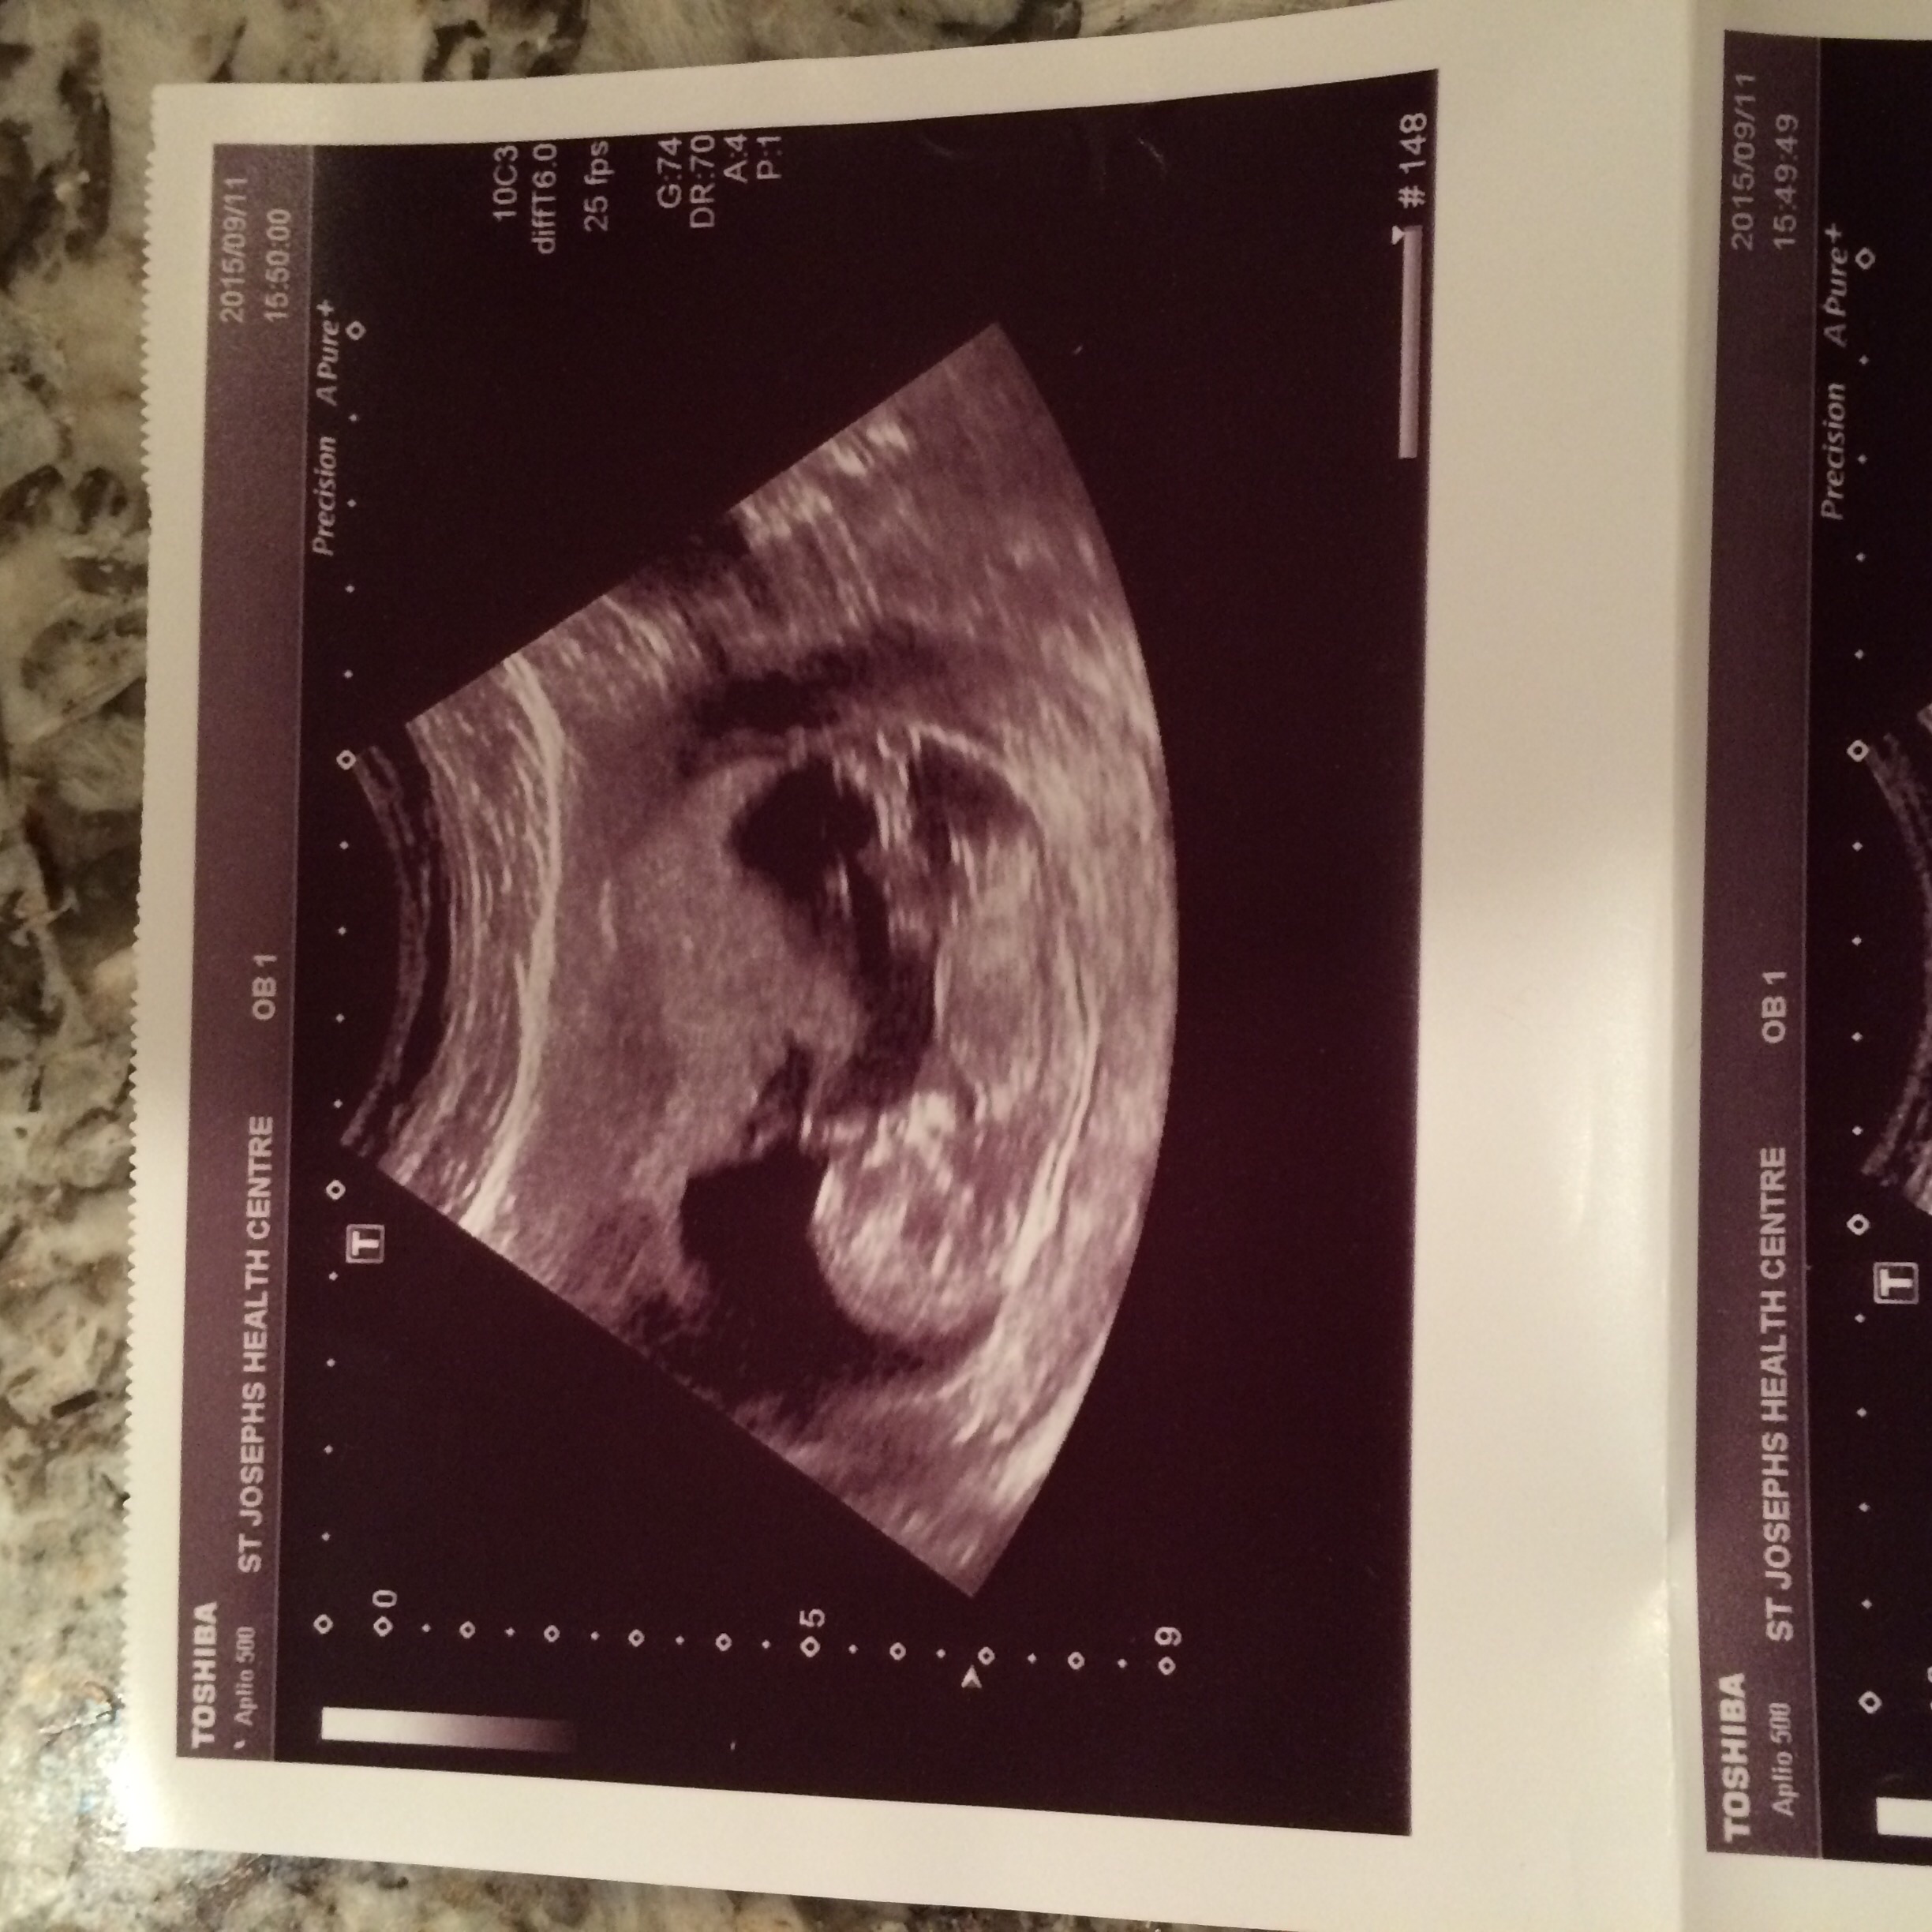

12w6dAttachment 27290:DS:Attachment 27291

These are all same baby lol between 12-12/6